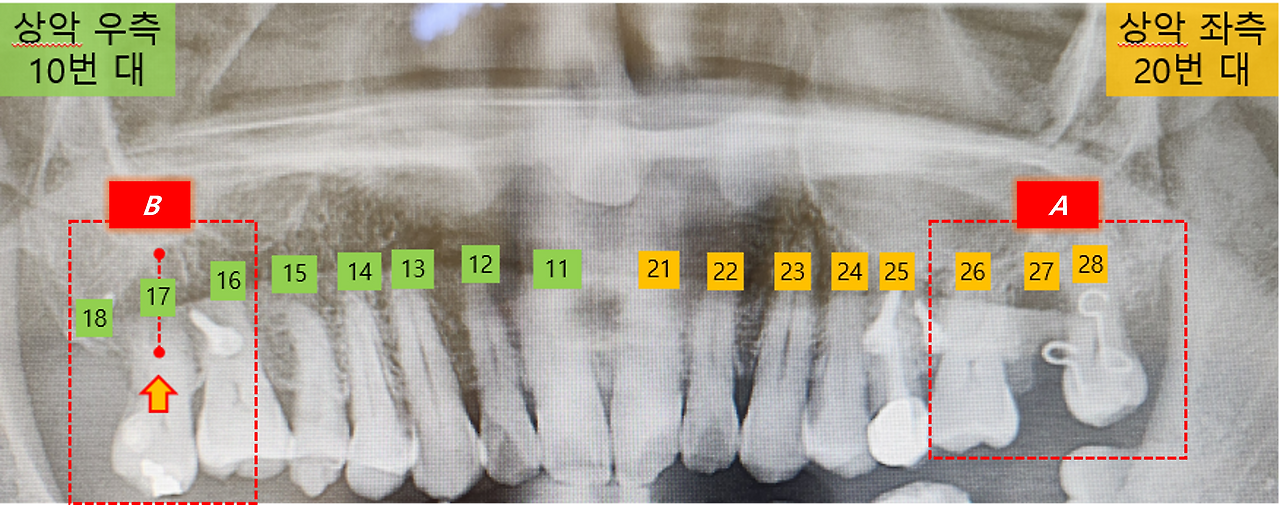

이제 파노라마 사진은 반대라는 정도는 아실 테니, 헷갈리지 않으셨으면 하네요.

먼저 상악 좌측(A) 교정 장치인 고리를 제거하는 일이 먼저입니다. 한번 떨어졌던 고리여서 본딩을 많이 했다고 하던데, 이를 제거하는 시간도 제법 걸리네요. 특히 본드가 잇몸과 치아 사이에도 있어 그라인딩으로 제거하는 과정에서 잇몸이 시큰거리는 느낌도 있습니다. 시큰거리는 느낌은 아프면서도 왠지 기분 나쁜 느낌이라고 할까요...

이번에 새롭게 부착할 고리는 이전보다 훨씬 긴 형태라고 합니다. 이는 28번 치아를 옆으로 당기다 보면 앞쪽(입술 쪽) 방향으로 치아가 움직일 수 있어, 반대로 뒤쪽(입 안쪽) 방향으로도 당겨야 하는 시간이 필요하다고 하네요. 그래서 이번에는 치아 안쪽에만 고리를 부착해 교정 스크루와 연결하는 방식으로 조정이 되었습니다.

한편 반대쪽(B)은 고무줄만 교체하는 것으로 간단하게 교정 기구 수정은 끝났습니다.

B 쪽(상악 좌측)은 기존과 큰 차이가 없어 불편함이 거의 없었지만, A 쪽(상악 우측)은 입천장 쪽에 닿는 긴 철사와 혀에서 느껴지는 까끌거림이 영 불편하게 느껴집니다.